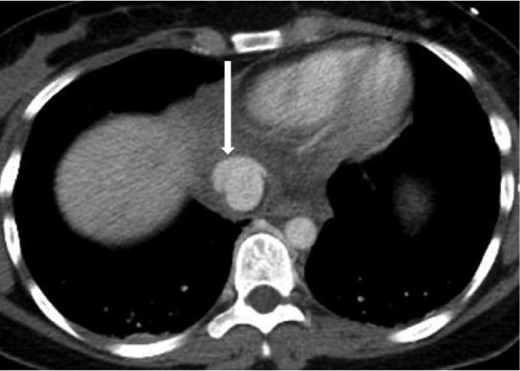

A 20-year-old female was the restrained driver of a vehicle traveling ∼45 miles per hour when her vehicle crashed into a city bus. She was extricated on scene by emergency responders and brought to the trauma bay alert, oriented and in stable condition complaining of pain on deep inspiration as well as left leg pain. She denied any abdominal pain or light-headedness. Vital signs on arrival were heart rate of 115 bpm, respiratory rate of 20 breaths per minute and blood pressure of 101/76 mmHg; her Glasgow coma scale was 15. The initial chest radiograph showed a small, right-sided pneumothorax and pulmonary contusions. Two radiographic views of the left leg revealed comminuted, mildly displaced tibia and fibula fractures. Computed tomography (CT) scans of the brain and neck were unremarkable. A contrast-enhanced chest CT scan demonstrated non-displaced right lateral second and third rib fractures, right upper lobe pulmonary contusions with laceration and a small pneumothorax, partially visualized grade 5 liver laceration with active contrast extravasation, and an acute, traumatic supradiaphragmatic IVC injury with an associated moderate hematoma and contrast extravasation that appeared to be contained, as seen in Figs 1 and 2. In view of incompletely imaged critical findings of the upper abdomen and continued hemodynamic stability of the patient, a dedicated abdomen and pelvis CT scan, seen in Figs 3–5, was performed 20 min later, which showed a stable 1.3 cm pseudoaneurysm of the supradiaphragmatic IVC without extension into the pericardium, stable moderate pericaval hematoma surrounding the injury, stable grade 5 liver laceration and a trace amount of fluid in the peritoneal cavity. A liver transplant surgeon and a cardiovascular surgeon were consulted due to the presence of acute traumatic suprahepatic IVC pseudoaneurysm.

Axial contrast-enhanced CT of the chest showing abnormal contour of the supradiaphragmatic IVC with ventrally and laterally confined contrast extravasation (arrow) consistent with a pseudoaneurysm surrounded by pericaval hematoma.